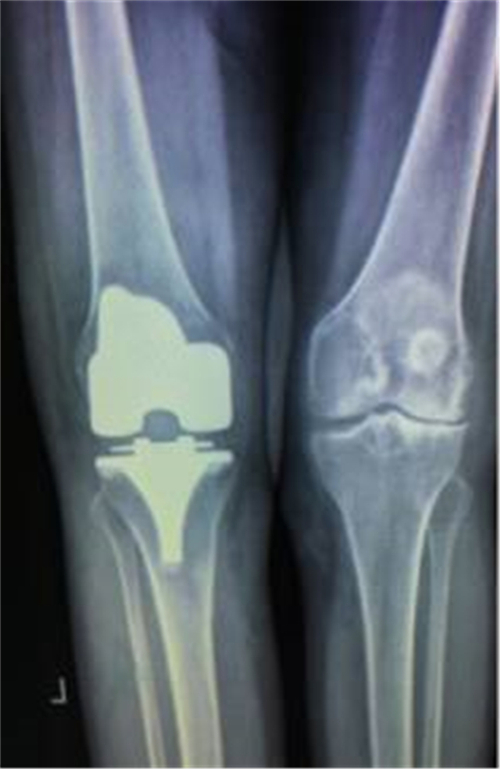

得知郴州市第四人民医院骨科掌握了这一手术技术,便前来就诊。谭主任接诊到该患者后,对其进行了详细的体魄检查,发现其左膝关节僵直,屈伸活动不能,负重时膝关节疼痛明显加重,膝关节X线片提示膝关节退变严重,关节间隙明显变窄,并有游离体形成,诊断为左膝关节重度骨关节炎并关节僵直,有明确的膝关节置换手术指征。

术前X线